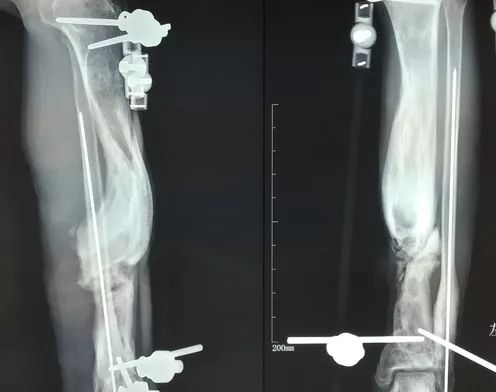

网友病例

这是一个网友的病例。首先感谢分享。

初次清创应该是用了止血带和双氧水,骨膜去除干净,白骨外露。外固定架固定骨折后一期闭合伤口。手术皮肤坏死,后期做了游离皮瓣。皮瓣感染坏死。

术中处理不当需要纠正的几点:

1. 清创不要用止血带,不要用双氧水。

2. 严重外伤皮肤张力大,没有把握不要一期闭合伤口,有潜在张力也不要闭合。

3. 感染未得到控制,或有潜在感染的可能不要做重建手术。

4. 尽量不要跨关节固定。

5. 感染伤口和不可避免的感染不能做重建手术——这是外科的定义。特殊情况可以突破定义但是要有确实可行的措施。